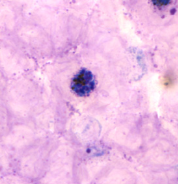

ENTAMOEBA HISTOLYTICA WITH CHROMATID BODY

Professor: Dr. Glena Fe A. Yapchulay-Alcabasa